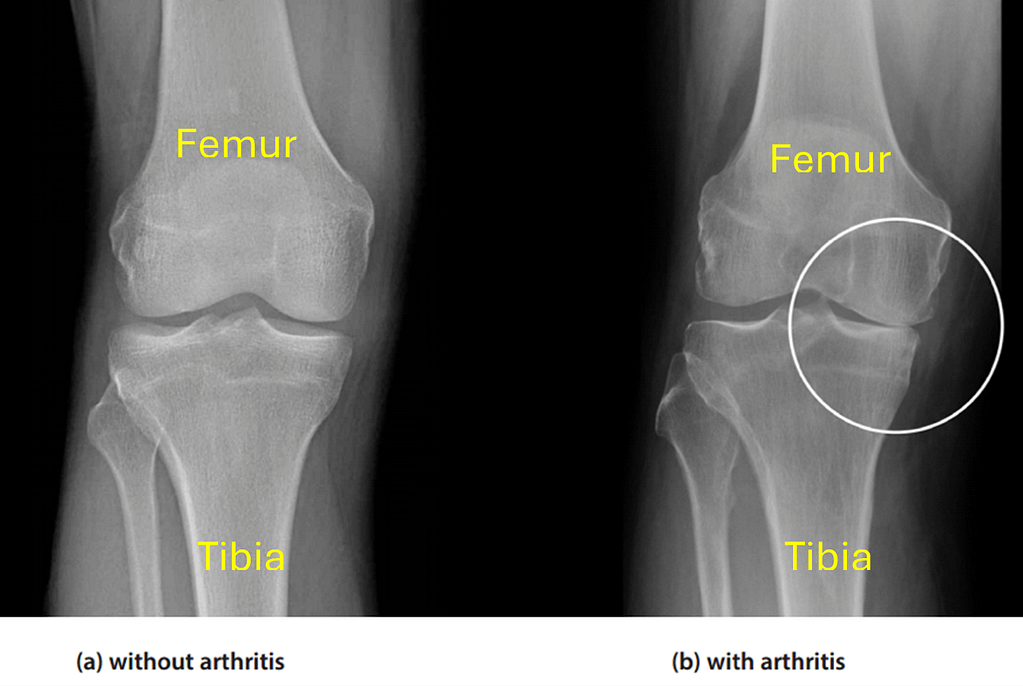

In the X-ray images here, the cartilage occupies the dark space between the ends of the femur and the tibia. In the left image, the cartilage is in normal condition but in the right image, it has worn away and thinned on one side. When the smooth articular surface of the tibia or the femur becomes worn through injury or overuse, the knee joint becomes painful to move. This condition is known as osteoarthritis. The knee may become stiff and some patients report that the knee becomes noisy, or “cracks” when it is used. Other symptoms may also include pain at night, stiffness first thing in the morning, and pain that is aggravated by increased use of the knee.